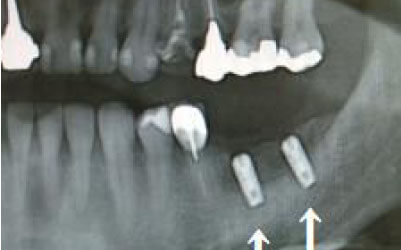

2 神経を傷つけるリスク

インプラントの手術では、顎の骨を通る神経を傷つけるリスクがあります。

しかし、事前にCTでしっかりと撮影し、三次元的に神経との距離を計測して治療計画を立てることで、心配は不要です。

また、当院では削りすぎを防ぐためのストッパーも使用しています。